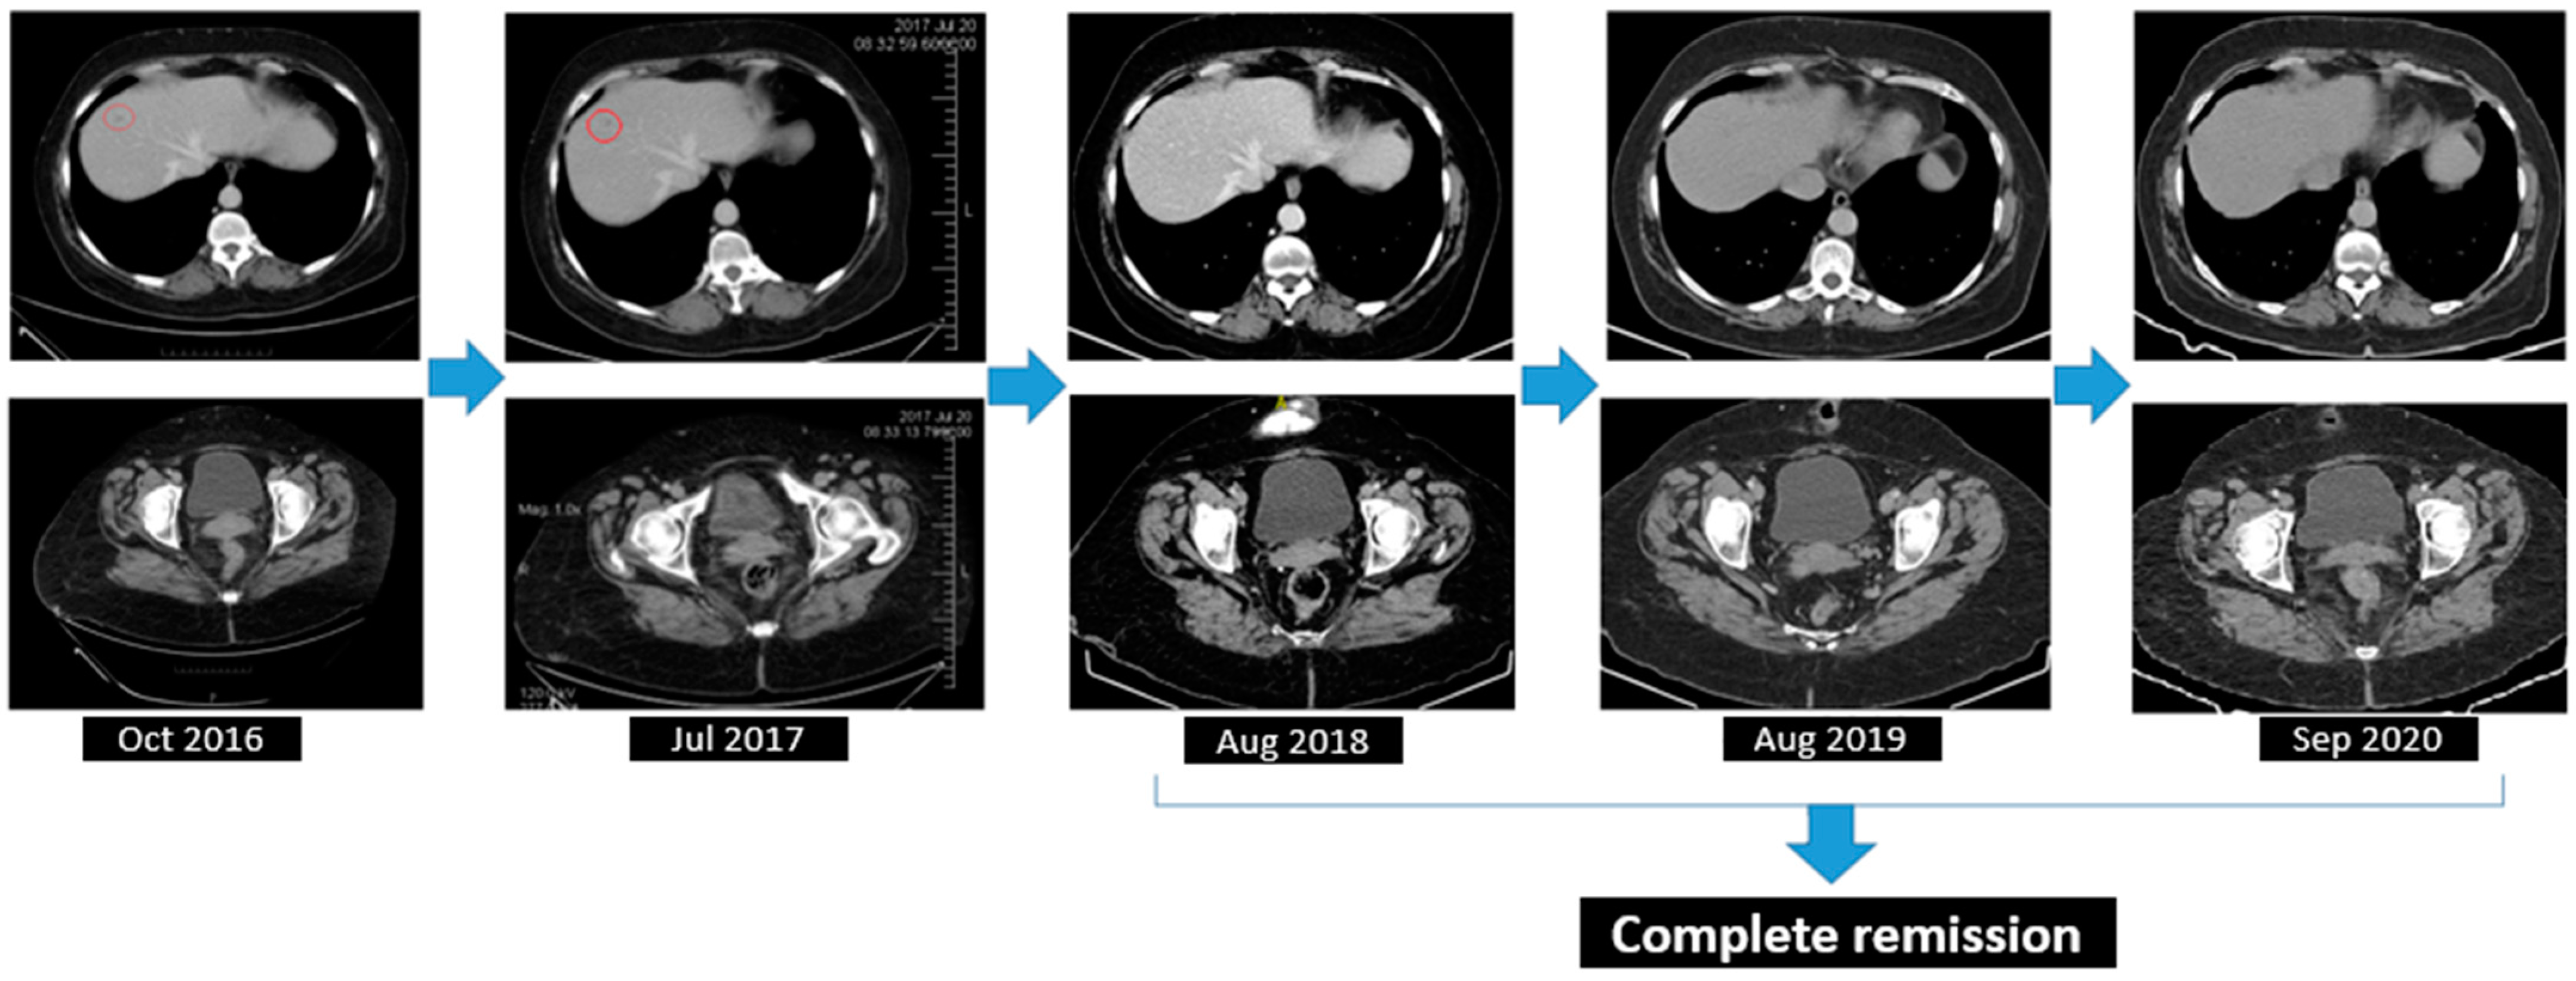

2.2.5. Treatment and Outcomes

2.2.6. Follow-Up

| October 2016 (start Olaparib maintenance) | 7.9 | 121,000 | 5.79 |

| October 2016–August 2018 (partial response under Olaparib therapy) | 9.5 * | 256,000 * | 7.80 * |

| August 2018–December 2021 (complete response under Olaparib therapy) | 9.7 * | 330,000 * | 12.70 * |

| January 2022 (progression) | 11.3 | 278,000 | 145.20 |

| June 2022 (after secondary cytoreductive surgery) | 10.1 | 488,000 | 18.65 |